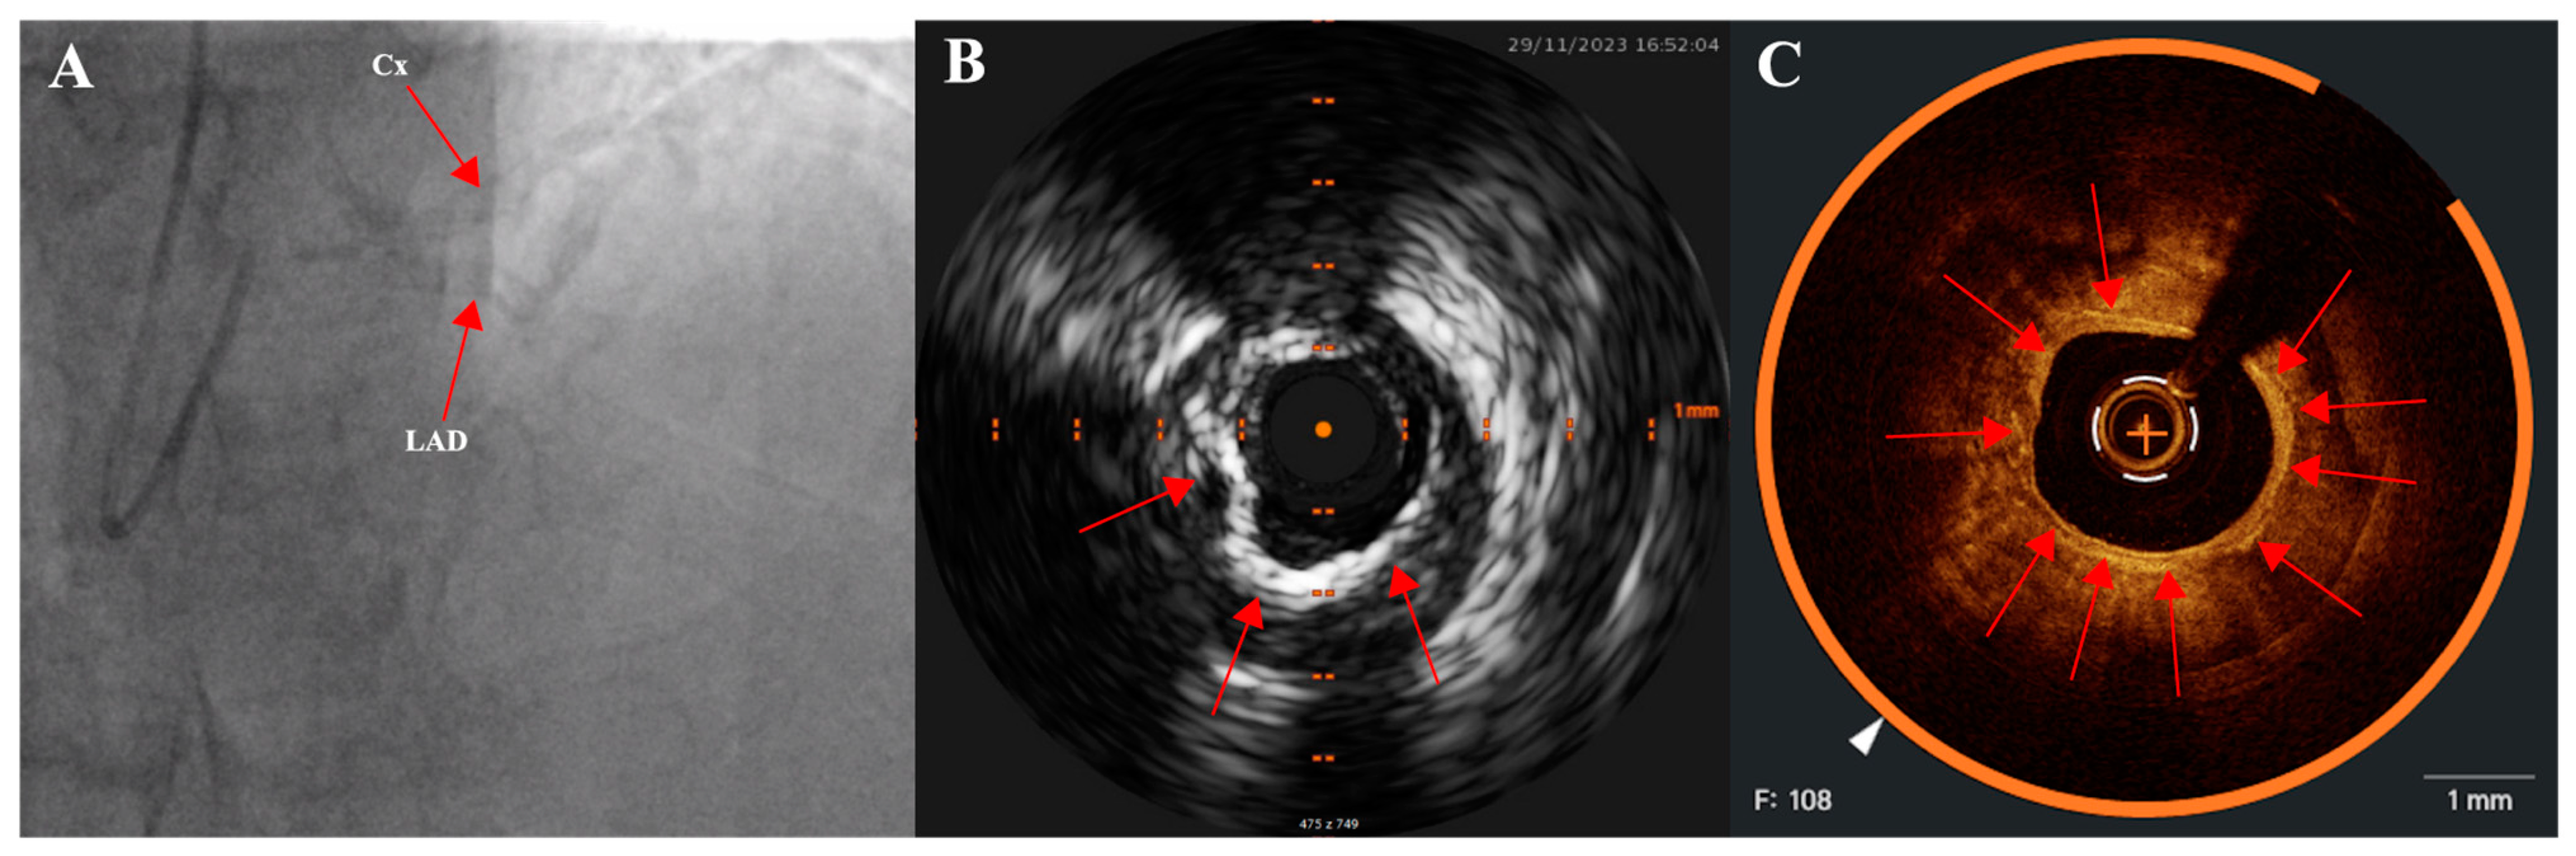

2.3. Intravascular Imaging: IVUS (Intravascular Ultrasound) and OCT (Optical Coherence Tomography)